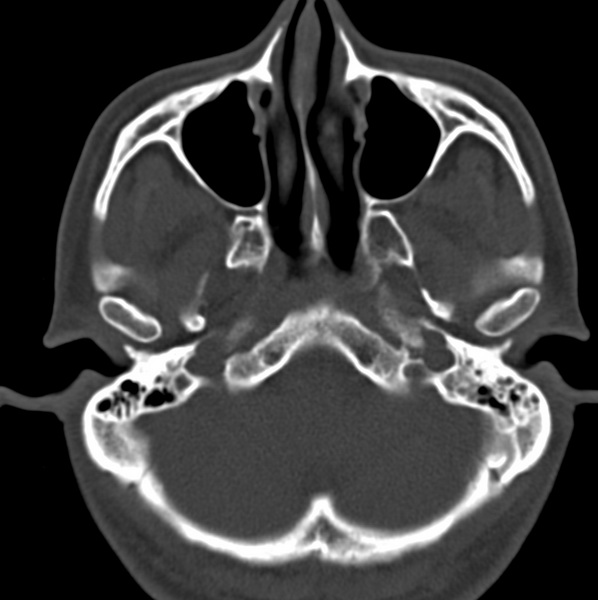

男、31、鼻咽部肿瘤放疗后请帮忙看看。

效果好,右侧破裂孔扩大,局部骨质缺损,为颅底骨质破坏。

1)鼻咽部肿瘤侵犯颅底放疗术后改变。2)左侧蝶窦炎。

咽后壁增厚,左侧咽鼓管隆突增大、咽鼓管咽口变浅,同侧咽旁间隙较窄。右侧颅底骨质破坏?为什么不在同一侧?

鼻咽部肿瘤侵犯颅底放疗术后改变.